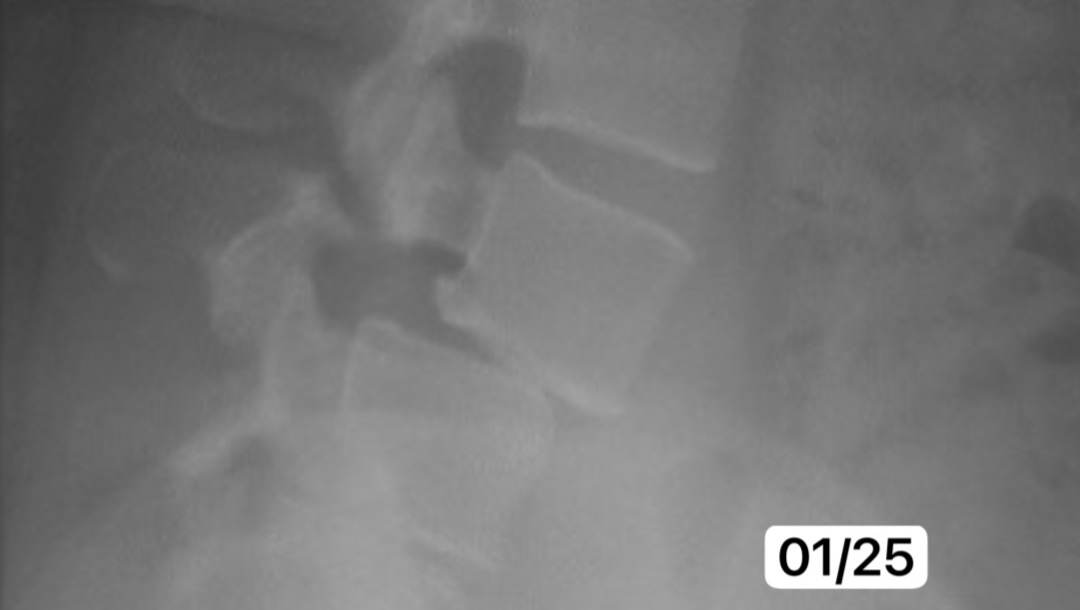

(Comparison x-ray January 2025)

As a result of this condition that I’ve had for many years now (and only officially diagnosed in February of 2024 via X-ray & MRI), I’ve also gained weight, which only worsens the condition and how I feel about myself. I want to lose weight, be healthy, get fit, and take my life back. However, I can’t do that until I can move properly again. Even worse, my spine is continuing to deteriorate, as shown in recent X-rays. If I don’t get this surgery soon, there’s a very real risk I’ll lose the ability to walk altogether.